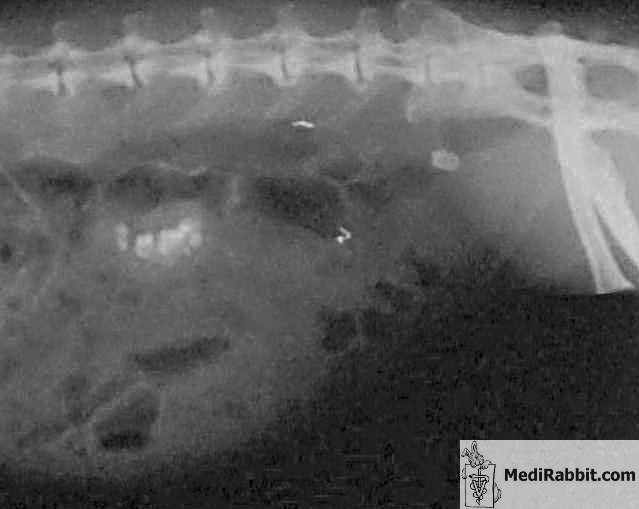

Katrina, a female albino rabbit,

years old, suffered from kidney stones, among other health problems. No

treatment exists, except removal of a kidney. After researching on this topic

with Susan L. (USA), we wanted to give it a try. Dr B. Langhofer